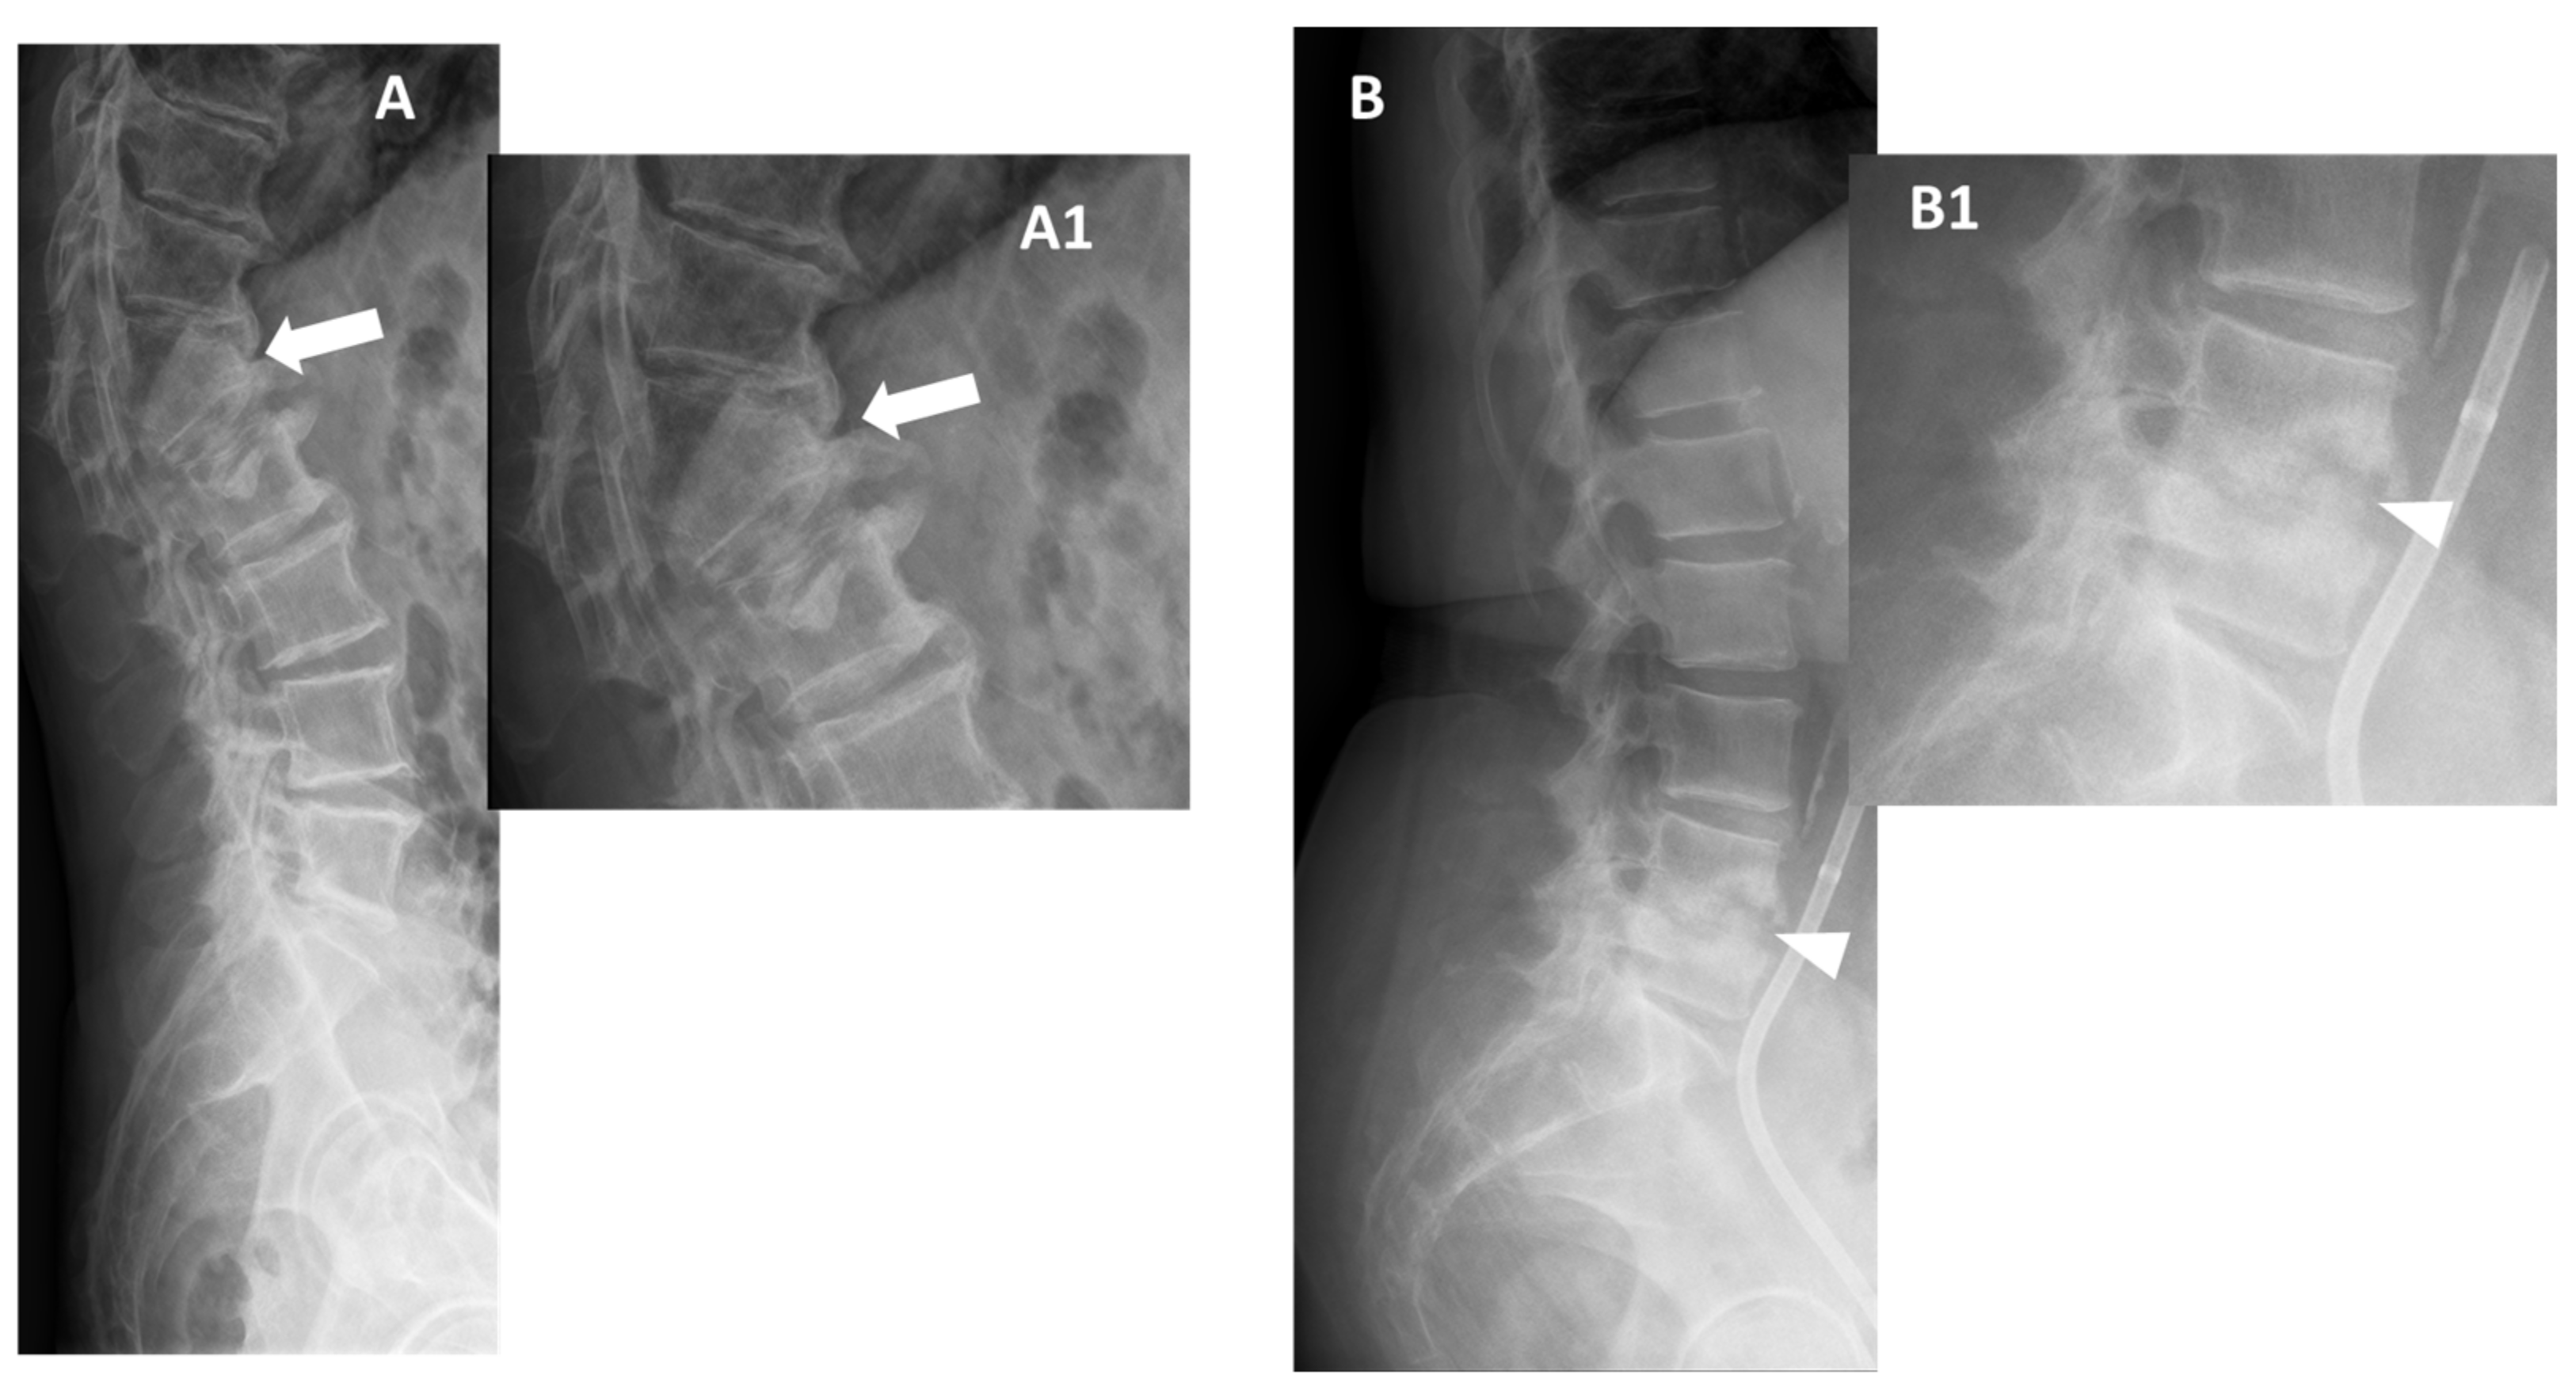

In the early stages of infection, specific radiographic markers are rarely evident, making it challenging to differentiate from degenerative pathologies. After 8 to 12 weeks, obvious destruction of bones can be observed (Figure 2) [32].

Figure 2. Conventional radiographs, lateral views (Panel A, and Magnification A1), of a 77-year-old male with previous pyogenic spondylodiscitis of T12-L1 vertebral bodies (partially collapsed and fused—arrows). Conventional radiographs, and lateral views (Panel B and Magnification B1) of a 64-year-old female with spondylodiscitis of L4–L5 vertebral bodies (thick endplate erosions are detected—arrowheads).